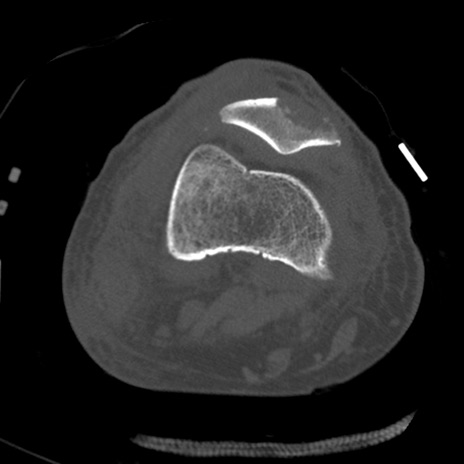

症例28 右膝関節CT(横断像)

右膝関節CT